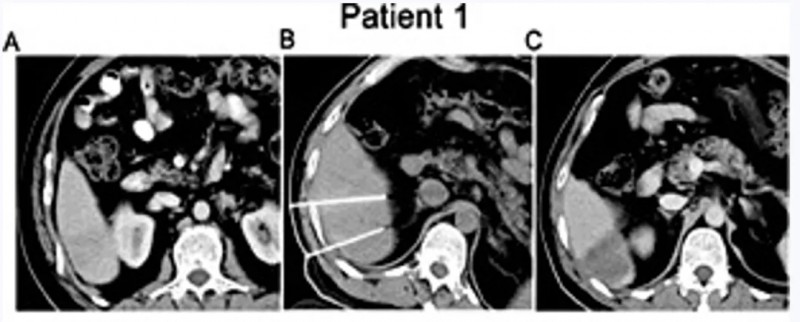

患者1:男性,44岁,2016年4月确诊IV期肝细胞癌,初始HCC结节最大直径3.5cm(详见下图A)。IRE+同种异体NK细胞联合治疗后MRI显示:占位性病变无强化(详见下图C),病灶区域轻度萎缩。

▲图源“Cell Physiol Biochem”,版权归原作者所有,如无意中侵犯了知识产权,请联系我们删除

患者2:女性,52岁,2016年7月入住复大肿瘤医院,IV期肝细胞癌,初始HCC结节最大直径3.0cm(详见下图A)。IRE+同种异体NK细胞联合治疗后MRI显示:病灶内可见大面积坏死(详见下图C)。